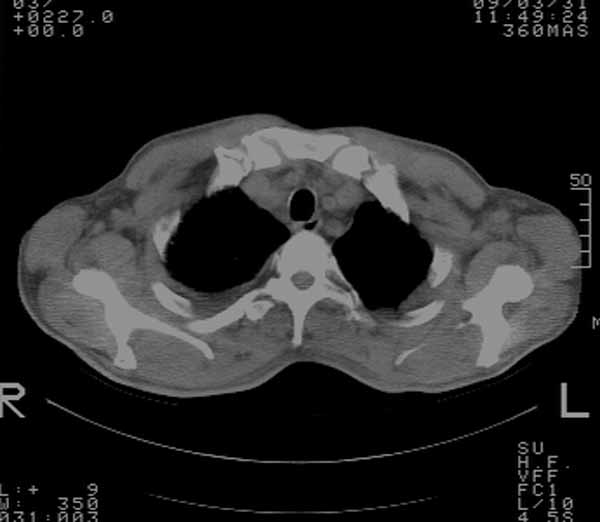

以下是引用余辉在2009-3-31 18:43:00的发言:[br]肺水肿,双侧心腔积液,心包积液,心影增大,疑似心衰

以下是引用wangyong1977在2009-3-31 20:46:00的发言:[br]肺水肿,双侧胸腔积液,心包积液,心影增大,疑似心衰 [br]

以下是引用宇宙ct在2009-3-31 18:57:00的发言:[br]肺水肿,双侧心腔积液,心包积液,心影增大,疑似心衰 [br] [br]